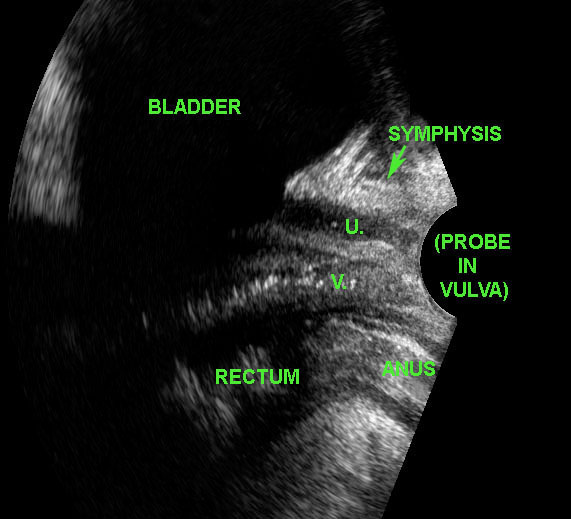

Túi thừa niệu đạo

Nhiễm trùng đường tiết niệu dưới tái phát có thể do tắc nghẽn/nhiễm trùng từng đợt của túi thừa niệu đạo. Ở người phụ nữ trẻ này, siêu âm đầu dò âm đạo (với đầu dò ở vị trí âm hộ) phát hiện một túi thừa niệu đạo lớn đang viêm (*) nằm bên phải và phía trước niệu đạo (U.) (V. và S. = âm đạo và khớp mu).

Xác nhận bằng MRI mặt phẳng đứng dọc và mặt phẳng đứng ngang.